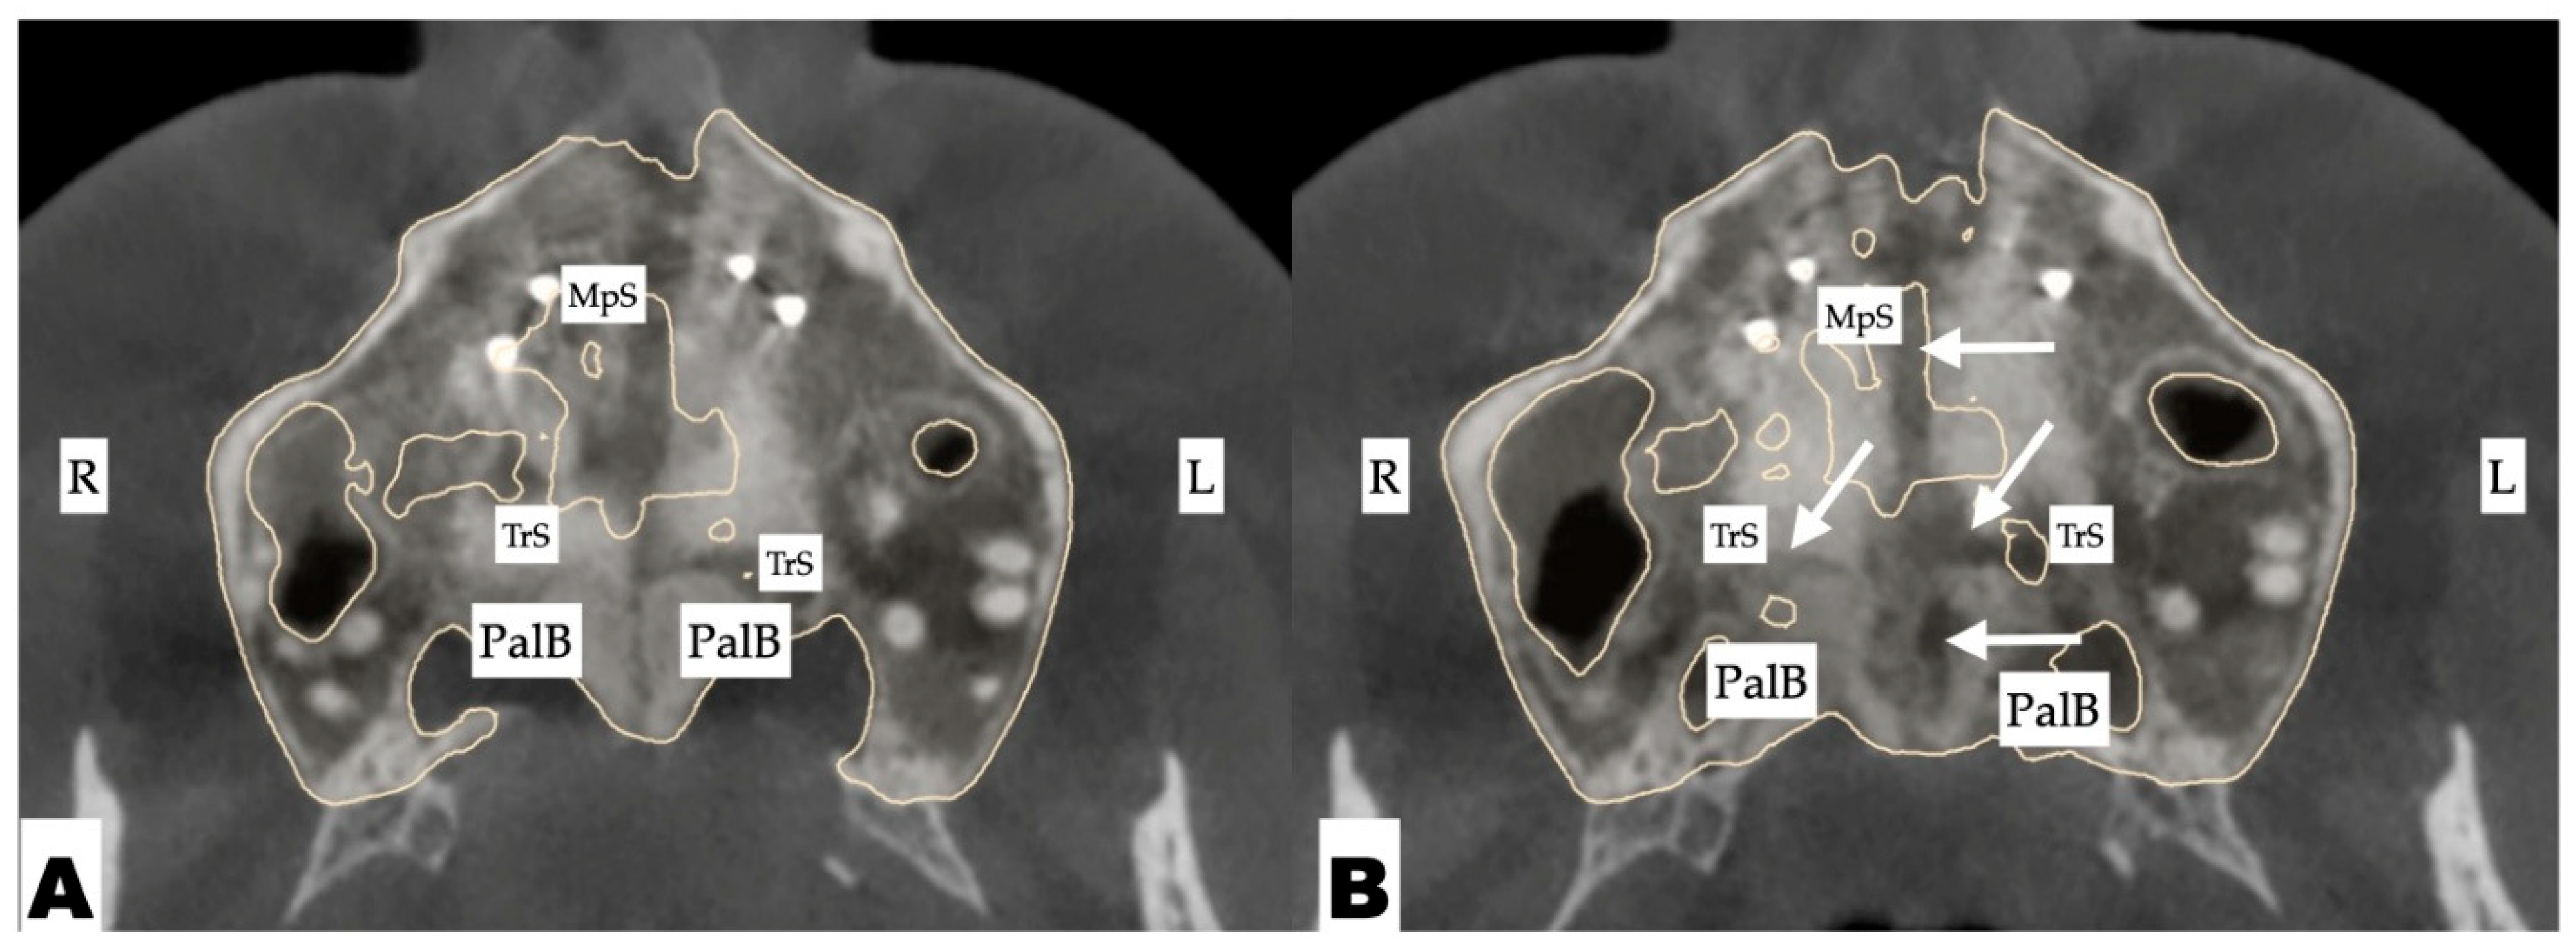

2.3.2. Design of 3D Surgical Guide

2.3.3. Osteotomy Planning and Appliance Design

2.3.4. Postoperative Assessment, Outcome Analysis, and Asymmetry Correction